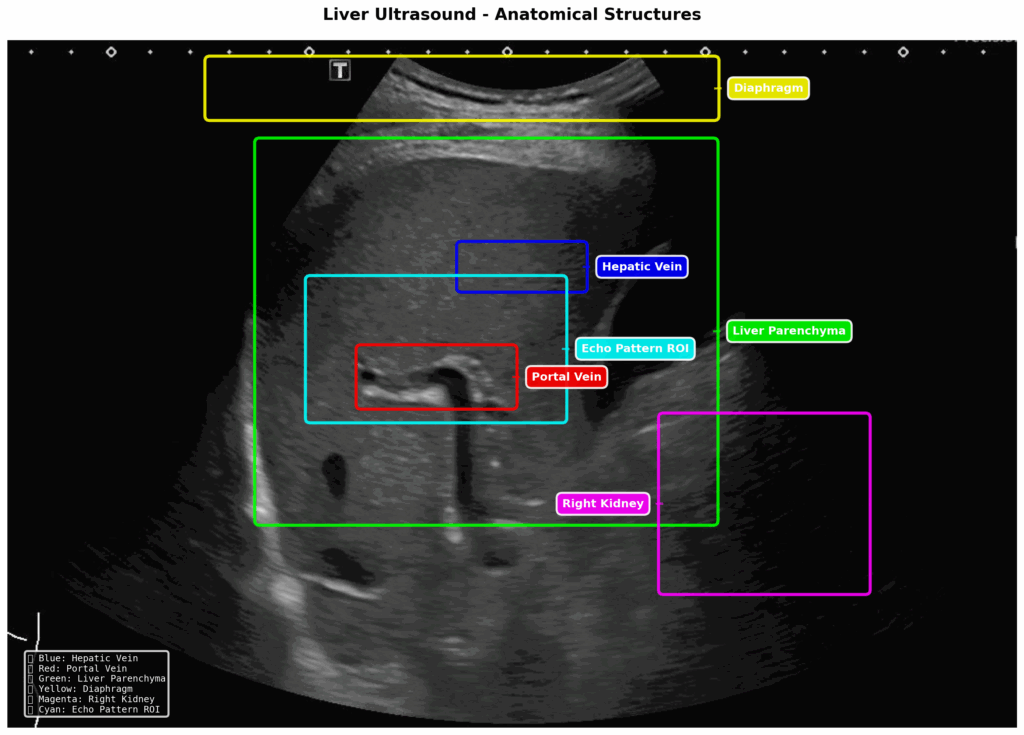

SmartLiva functions as a digital upgrade for standard black-and-white ultrasound scans. By uploading images to a web-based platform, the AI enhances the visual clarity, isolates the liver tissue, and applies color-coded highlights—such as red for the liver and yellow for fat—to make abnormalities immediately visible. The system evaluates three key areas simultaneously: liver fibrosis stages (F0–F4), tissue abnormalities like cysts or tumors, and the presence of liver flukes, eventually generating a comprehensive report for medical staff.